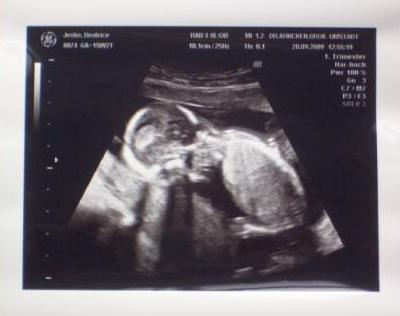

HI, auf dem hier liegt er mit dem Gesicht nach unten... LG Bea

Bild zu US Bilder von gestern - Forum für März - Mamis